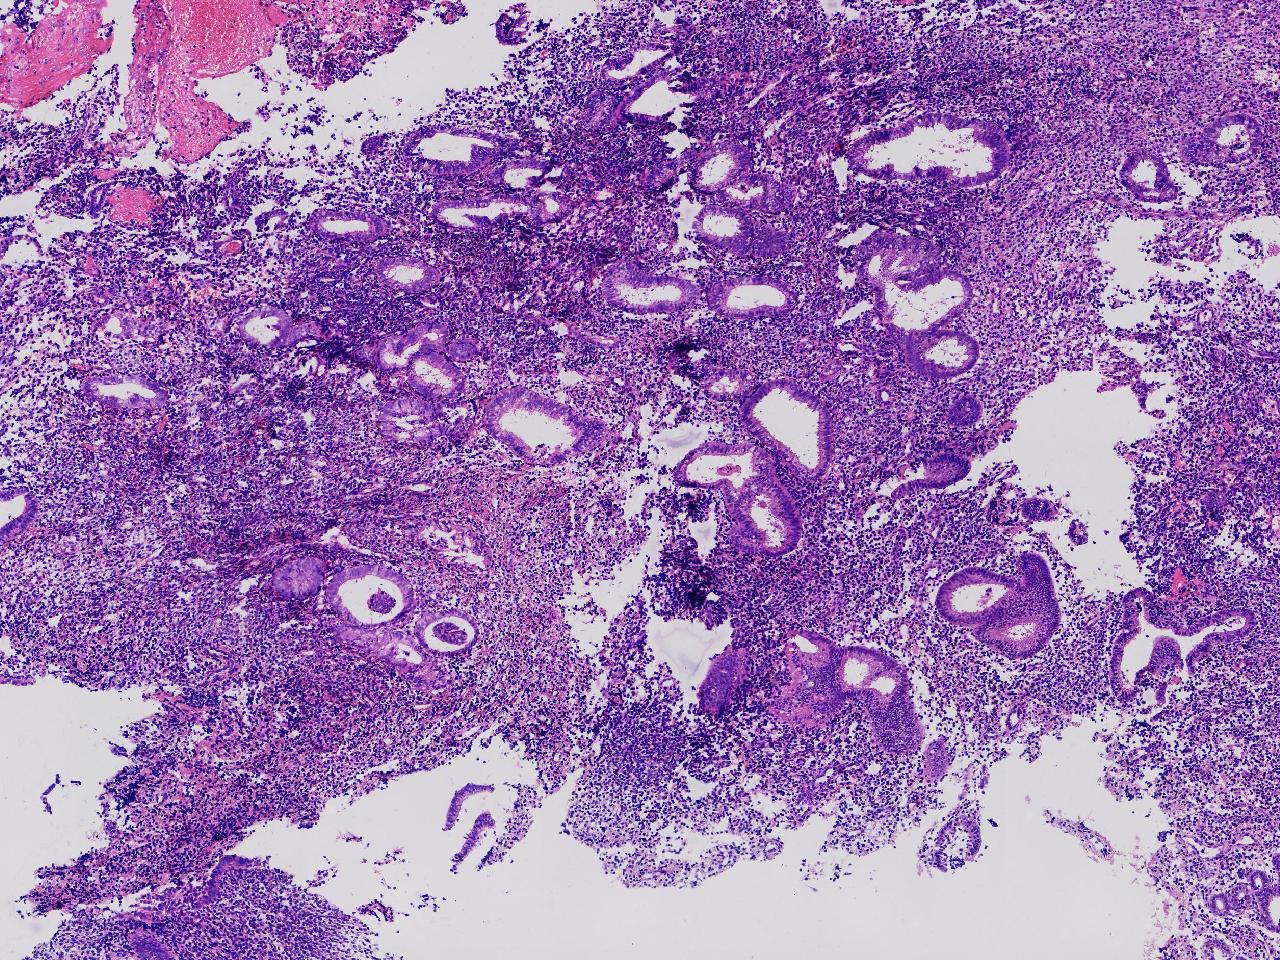

请教诊断。局灶够不够非典?

性别

女

年龄

44岁

阴道不规则出血20余日,彩超示:内膜线居中,厚15毫米。

子宫内膜

灰粉色不整形软组织多块,3X2X1厘米。

不够非典

有输卵管上皮化生,感觉不够非典。